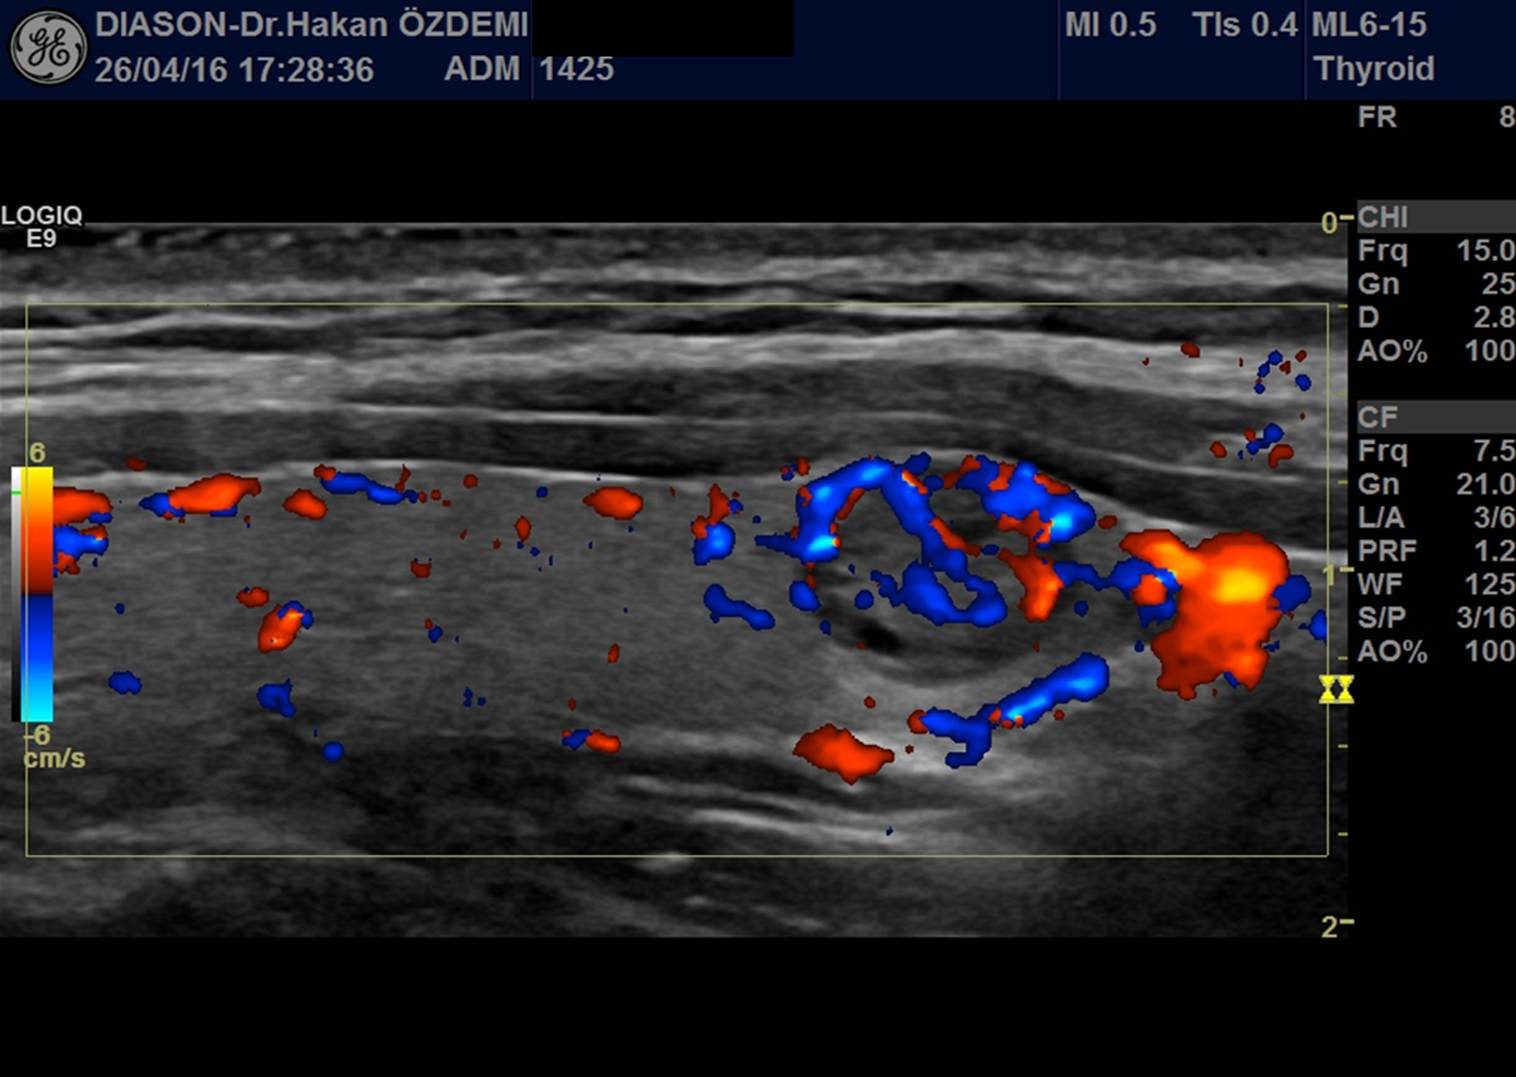

Doppler ultrason, bir organdaki veya damardaki kan akımını incelemek için kullanılan özel bir ultrason görüntüleme yöntemidir. Kan akımının miktarı, hızı ve yönü değerlendirilebilir. Akan kan, kırmızı ya da mavi renkte izlenir. Kanın akım hızı ve miktarı ile ilgili ölçümler yapılırken cihazdan kalp atışlarına benzer sesler duyulmaktadır. Cihazın çalışma prensibi, sesin hareket eden yapılardan yansırken frekans değişikliği göstermesidir.

Doppler incelemesi ile damarlardaki daralma, tıkanma ve akım değişiklikleri gibi durumlar saptanabilmektedir. Doppler ultrason incelemesi, farklı bilgisayar donanımına sahip ultrason cihazları ile yapılır.

Doppler ultrason incelemesi ile kol ve bacak damarları, karaciğeri besleyen damarlar, böbreği besleyen damarlar, boyun damarları, gebelerde anneye ve fetusa ait damarlar, erkeklerde testisleri besleyen damarlar, gözü besleyen damarlar, vücudun herhangi bir bölgesinde oluşan bir kitlenin damarlanması incelenebilir.